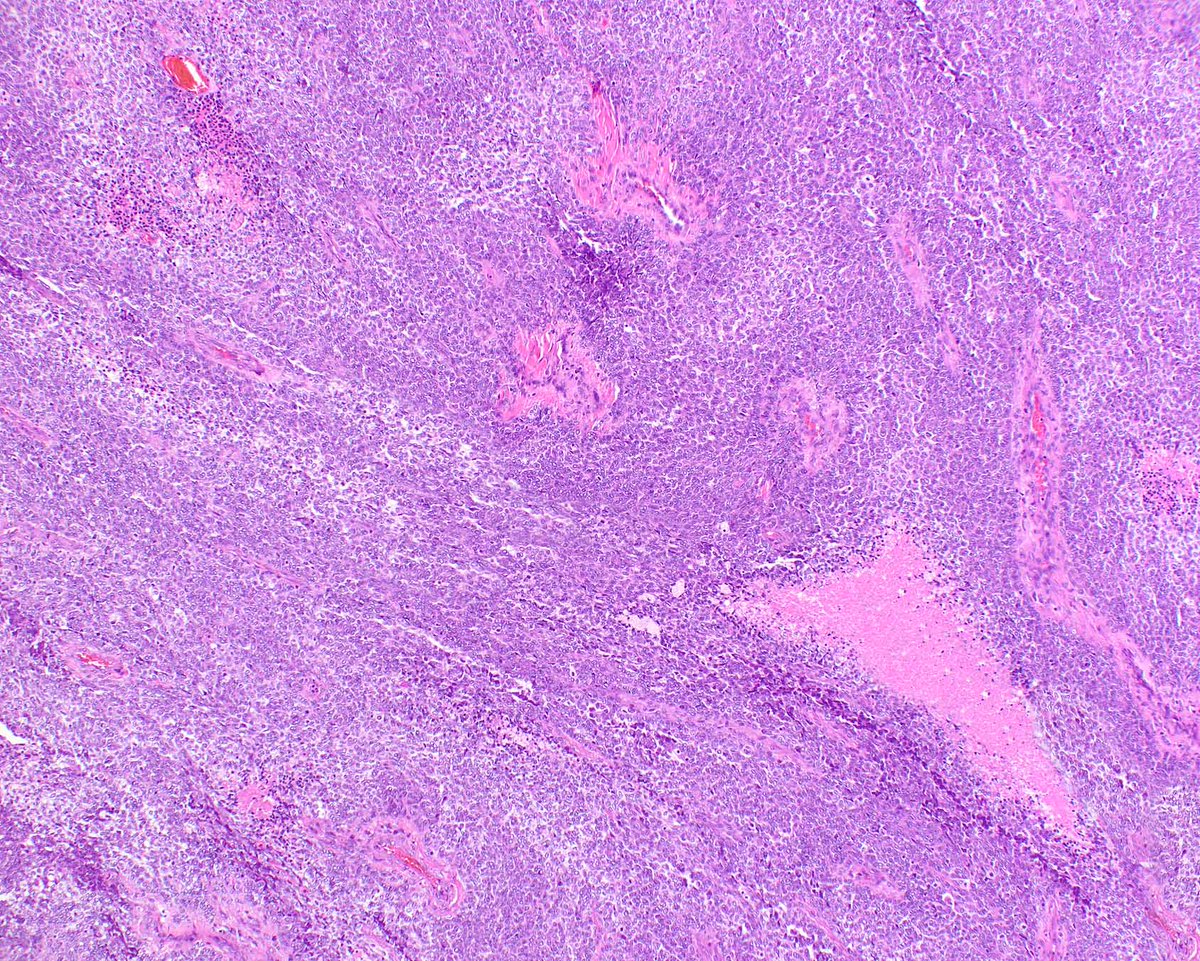

Proposed model for pathogenesis of malignant Brenner tumors of the ovary based on our study in @ModernPathology. Resemblance to #urothelial carcinogenesis and potential anti-FGFR3 targeted therapy implications (#erdafitinib). #OvarianCancer. Article link: rdcu.be/b8IFc